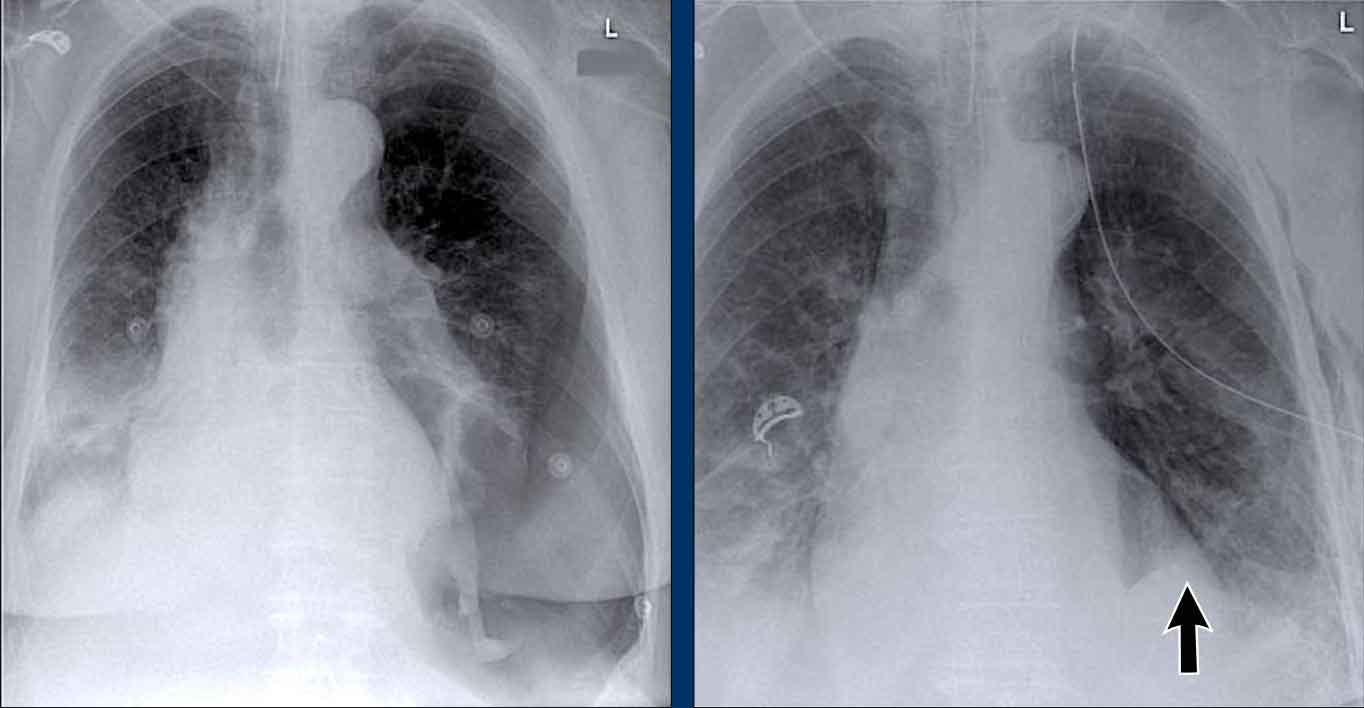

Displacement of the Azygoesophageal Line (1) – Hiatal hernia

A hiatal hernia (arrowheads) is the most common cause of displacement of the azygoesophageal line as seen on the PA-view.

Notice the air within the hernia on the lateral view (black arrow).

Displacement of the Azygoesophageal Line (2) – Subcarinal Lymphadenopathy

A common cause of displacement of the azygoesophageal line is subcarinal lymphadenopathy (station 7).

On the chest X-ray, note superior displacement of the azygoesophageal line just below the carina, consistent with enlarged subcarinal lymph nodes (black arrow).

Additional right paratracheal lymphadenopathy is seen, displacing the right paratracheal stripe (white arrow) and deviating the trachea to the left.